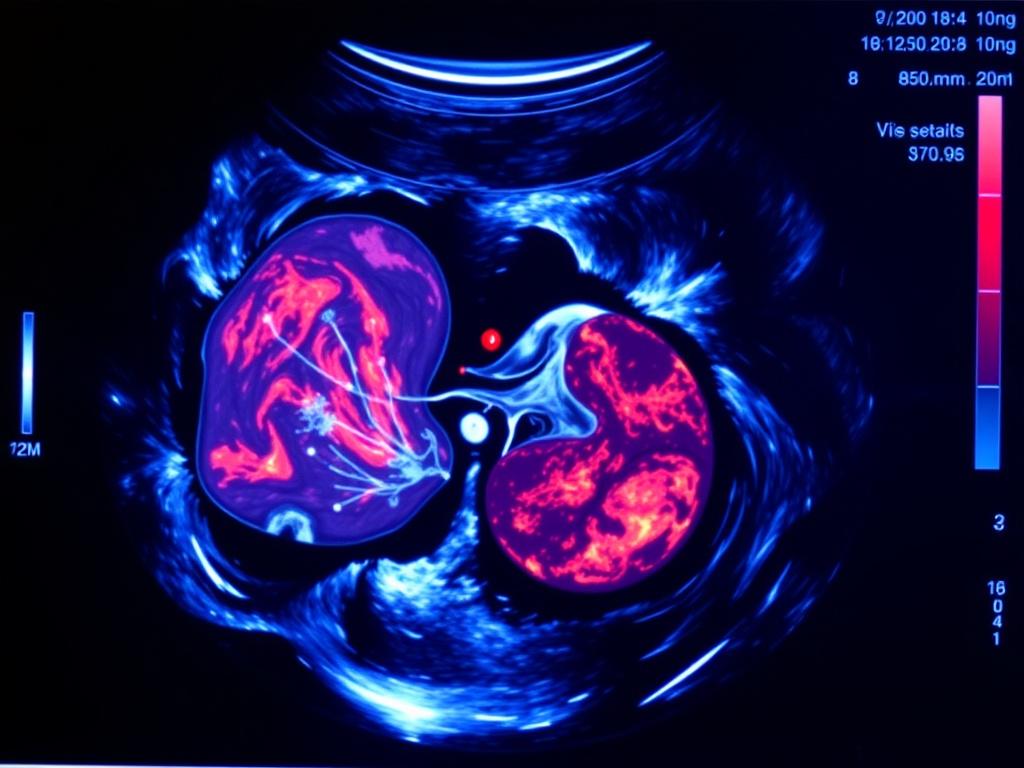

Ультразвуковое исследование предстательной железы проводят двумя основными способами: трансабдоминально и трансректально. Каждый имеет свои преимущества и ограничения, и врач выбирает метод исходя из клинической задачи и анатомии пациента.

Это наружное сканирование через переднюю брюшную стенку. Аппарат ставят на живот, исследование безболезненное и обычно комфортно переносится. Метод хорош для оценки объёма железы и состояния мочевого пузыря, в плане общей картины он информативен, но чувствительность ниже, чем у трансректального доступа, особенно при небольших узлах или ранних опухолевых очагах.

Здесь датчик вводят в прямую кишку, что обеспечивает более близкое приближение к предстательной железе и лучшую детализацию. TRUS позволяет измерять объём, оценивать внутреннюю структуру, обнаруживать подозрительные участки и проводить биопсию под контролем изображения. Процедура вызывает некоторый дискомфорт, но обычно не болезненна. При необходимости выполняют местную анестезию или назначают антибиотики перед манипуляцией.

Что оценивают при УЗИ: структура, объём, зоны

Врач измеряет три линейных размера железы — продольный, поперечный и переднезадний — и рассчитывает объём по формуле для эллипсоида: объём = длина × ширина × высота × 0.52. Объём используется для расчёта плотности PSA, то есть PSA делят на объём железы, это помогает отличать увеличение PSA из-за большого объёма от реального риска опухоли.

Также оценивают зону периферической и переходной зоны, эхогенность ткани и наличие узлов. Рак простаты часто выглядит как гипоэхогенное (более темное) пятно в периферической зоне, но такие изменения не всегда означают опухоль — возможны воспалительные процессы и другие состояния. Важна клиническая корреляция и иногда подтверждение биопсией.